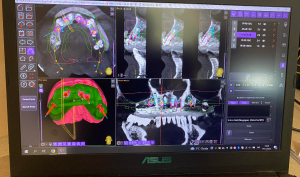

Перед імплантацією пацієнт проходить повну діагностику ротової порожнини, оцінюється стан кісткової тканини, проводиться повна санація порожнини рота(професійна чистка, лікування карієсу, видалення нежиттєздатних зубів).

Іноді перед імплантацією необхідні додаткові  підготовчі процедури, такі як: синусліфтинг або направлена кісткова пластика, про це лікар Вам повідомить після детальної діагностики стану кісткової тканини .